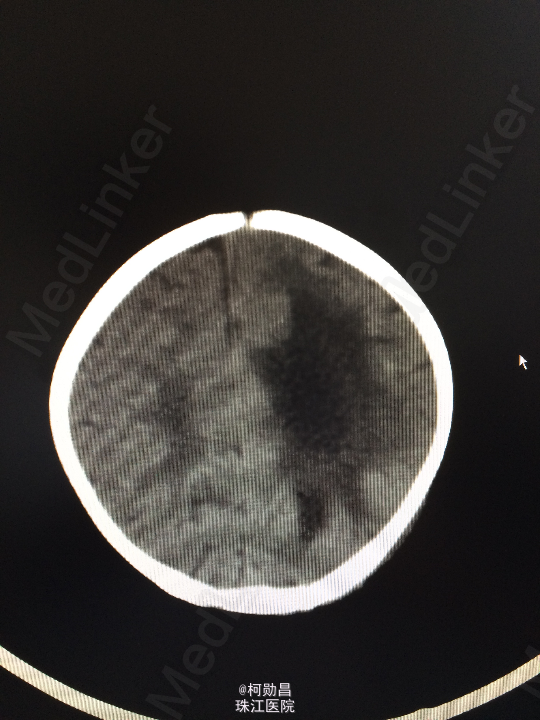

查体:神志不清,四肢肌力增高 辅助检查:头颅CT提示脑积水并脑脊液外渗,幕上脑室扩张,右侧额颞叶硬膜下脑脊

诊断:化脓性脑膜炎伴脑积水 处理:予内科抗感染治疗,后行脑室腹腔引流术。